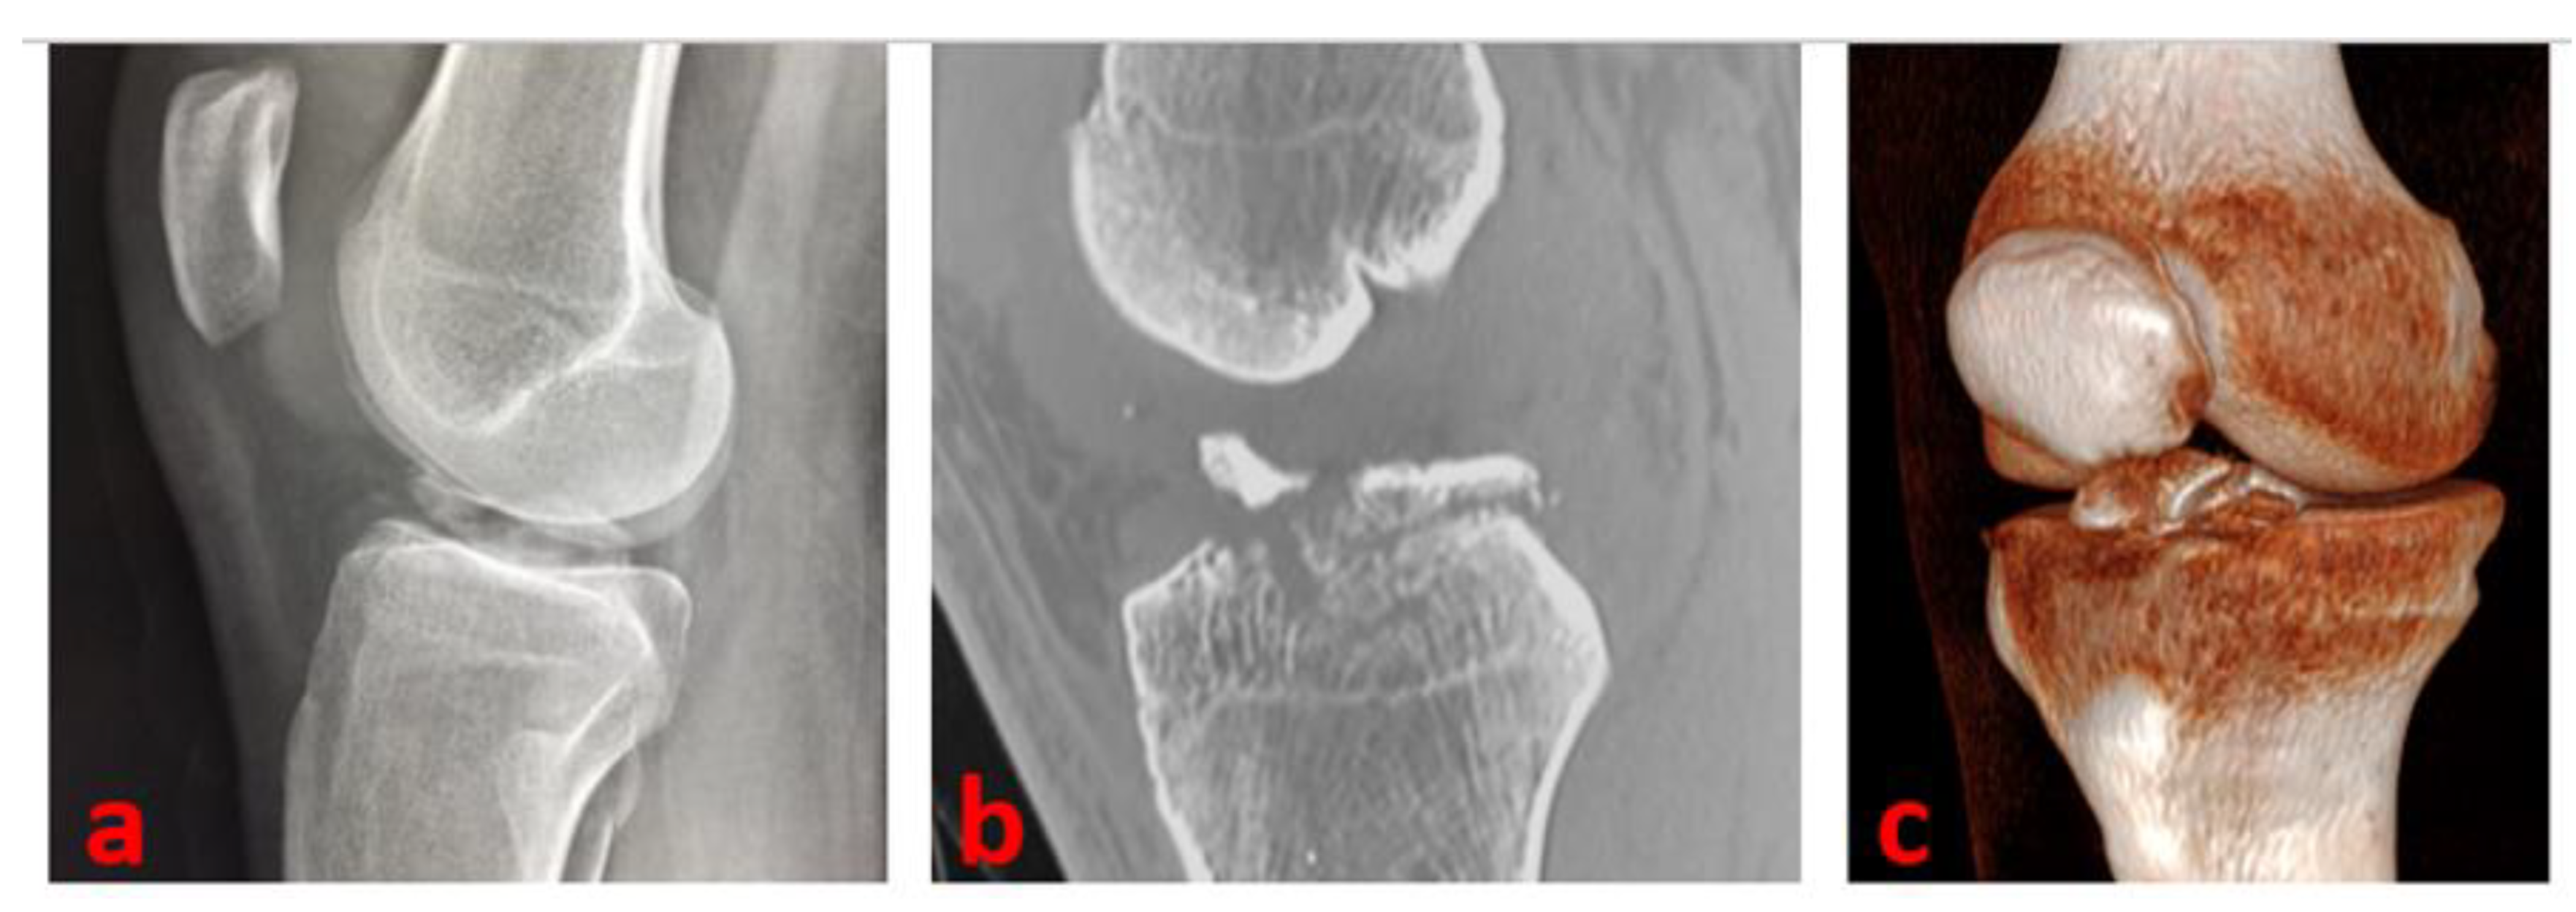

A complete radiographic knee series with AP, lateral, tunnel, and Merchant views is a major support. A true lateral view with the knee in hyperextension is useful in determining the reducibility of the fragment; it helps us, especially in the case of type II avulsions. The radiographic series can be integrated with a CT scan (to further delineate the fracture pattern: size, shape, fragmentation, and comminution) and MRI (to assess for associated intraarticular injuries) [10]—(Figure 1).

Figure 1.

A true lateral knee radiographic view of the right knee of a 16-year-old male patient of our series shows a Type 3 tibial avulsion fracture (a); CT scans are useful to define the pattern of the fracture and drive the management: CT sagittal view scan (b) and 3D CT reconstruction (c) of the same patient.